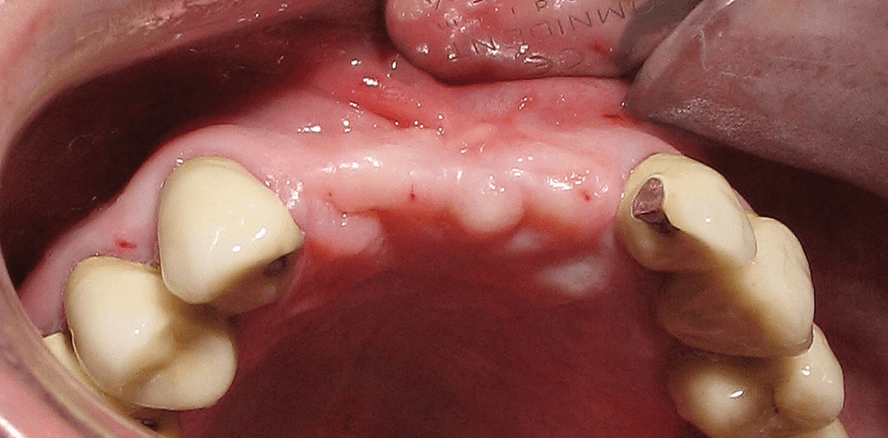

In diesem Fall ist ein ausgeprägter lateraler und vertikaler Defekt in der anterioren Maxilla zu sehen (Abb. 1–4). Vor allem die Region 12 bis 11 zeigt eine defizitäre Knochenhöhe von circa 4–5 mm. Eine Implantation mit simultanem Aufbau wäre in Regio 21 möglich. In Regio 22 wäre ein Aufbau nur mit dem Kompromiss einer sehr langen Krone möglich – eine herausnehmbare Versorgung wäre unakzep­tabel. Die Entscheidung fiel auf ein zweizeitiges Vorgehen. Die Knochenbreite betrug bei 12 circa 2 mm und bei Zahn 22 circa 3 mm (Abb. 5 und 6). Das benötigte Volumen betrug mindestens 6–8 mm lateral und circa 4 mm vertikal. Die Augmentation erfolgte mit einer Kombination von autologem Knochen, resorbierbarem Allograft und HA (Abb. 7 und 8). Der höhere Anteil von HA diente der vertikalen Stabilität des Augmentats und dem langfristigen Erhalt während der Einheilphase. Die Membran war eine kreuzvernetzte Kollagenmembran mit langer Resorptionszeit und wurde in diesem Fall gepinnt.